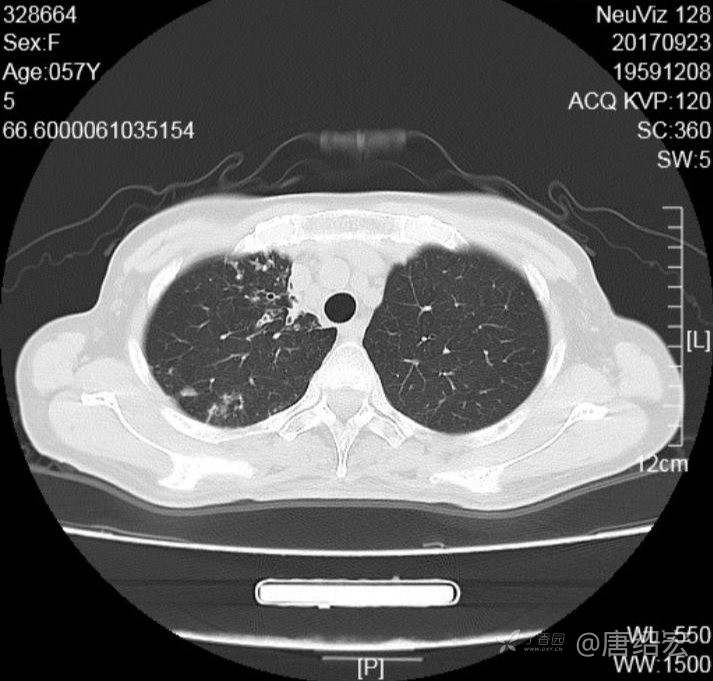

女,57岁,

主诉:发热、咳嗽、咯黄痰,胸闷3天入院。

铜绿假单胞菌性肺炎 (12)

铜绿假单胞菌感染 (20)